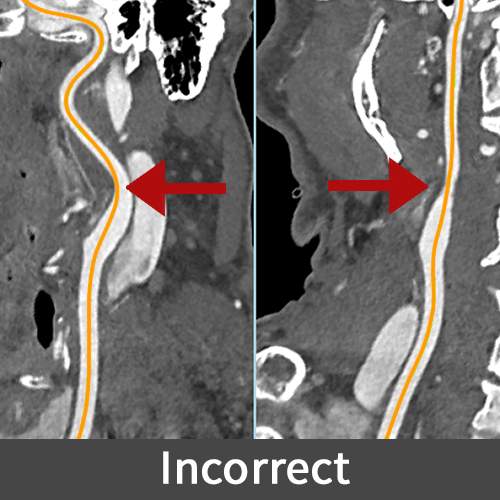

Curved Planar Reformation (CPR) is an imaging technique that reformats 3D data into 2D images along curved structures like blood vessels, aiding in the treatment of various conditions. It is crucial for visualizing aneurysms for precise surgical planning, delineating blood vessels in brain cancer for safer tumor removal, and assessing narrowed arteries in Moyamoya disease to guide effective surgical interventions.

An off-centered centerline in a CPR can lead to inaccurate diagnoses and flawed surgical planning, as it may misrepresent the size, shape, and course of anatomical structures. This inaccuracy poses risks during surgical interventions, potentially causing complications and delays in treatment, and may reduce patient confidence in the diagnostic and treatment process.

Figure D (Right): A misaligned and properly aligned center-line of a CPR.